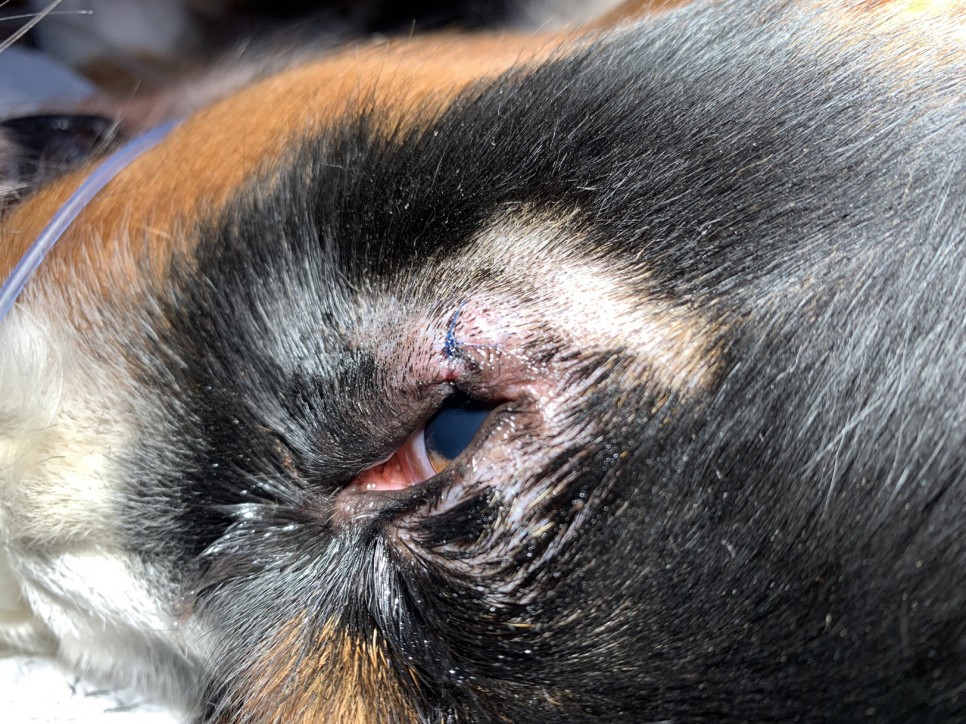

그동안 미뤄왔던 안검 종괴도 같이 제거됐습니다